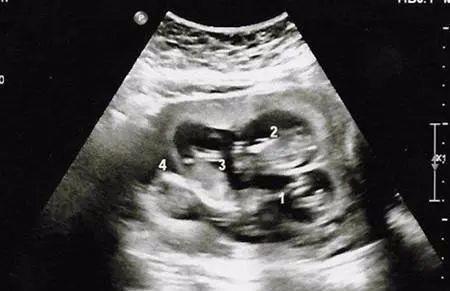

孕12周以后大如“临盆”,邻居亲朋都说不会是怀上双胞胎了吧,小蓉也只是笑笑,心想要是有就好了,当第一次产检时,医生却笑着恭喜说:“你是怀上了四胞胎了,我建议你最好减胎。”,全家人听完顿时愣住了。